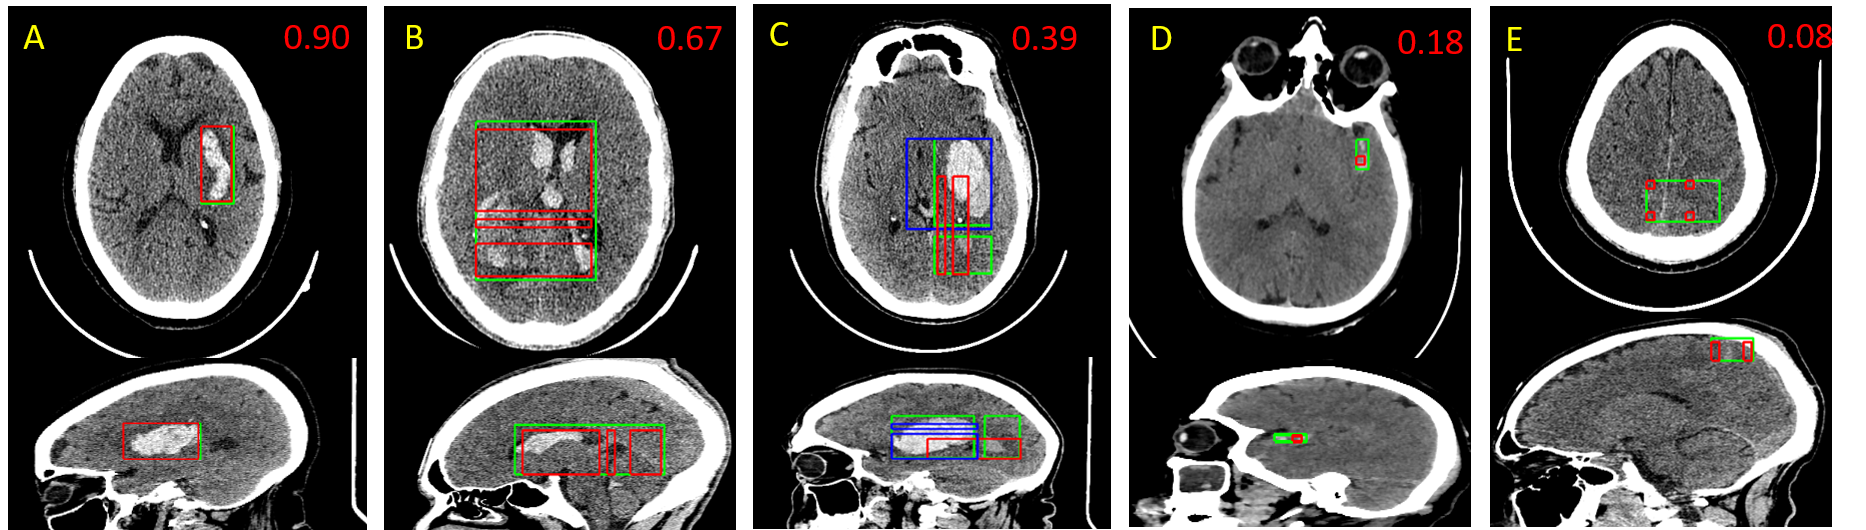

The IoU value can be low for tiny detected objects, although by subjective evaluation it seems to be a correct localization (Fig. 2 D); the slight difference in the position of BBs causes a distinct decrease in their relative overlap.

Based on achieved sensitivities (Table 1) it is evident that the algorithm provides more false-negative cases; thus the ICHs are not detected or, more frequently, were detected inaccurately (Fig. 2 D E). It could have been caused by an unbalanced number of positive and negative images in the training dataset (negative cases were up to five times more frequent than positive ones). In contrast, it caused a lower number of false-positive cases and higher PPV.

The CNN models can distinguish various types of haemorrhages despite their different position, size and shape variability, hence the proposed algorithm can localize the ICH and provide its label even in case of small hemorrhages (see Fig. 2 D).

Despite small amount of data with IVH, the results are similar to other types, which may be caused by their characteristic position and shape (see Fig. 2 B), which is given by the ventricles of brain. Lower results of SDH may be caused by the problematic detection in sagittal and coronal direction. In addition, it is observed that EDHs may sometimes be confused with SDHs (which may be a problem even for a human observer, mainly in sagittal and coronal slices).

The main benefit of the proposed architecture is locating and classifying ICHs, even in cases of the appearance of multiple sub-types of ICHs (Fig. 2 C). There can be predicted more FN cases if the image contains small ICH and large ICH of another type.

Figure 2: Axial and sagittal views of resulting bounding boxes of the algorithm testing compared to ground truth (green) together with the IoU value (in the right upper corner). A – bounding box of IPH (red) matching well with ground truth, B – result of IVH localisation (red), C – localisation of multiple hemorrhage types: IPH (blue) and IVH (red) with the total IoU for both types jointly, D – small SAH localization (red), E – poorly located SAH with small overlap between the found bounding box and ground truth.